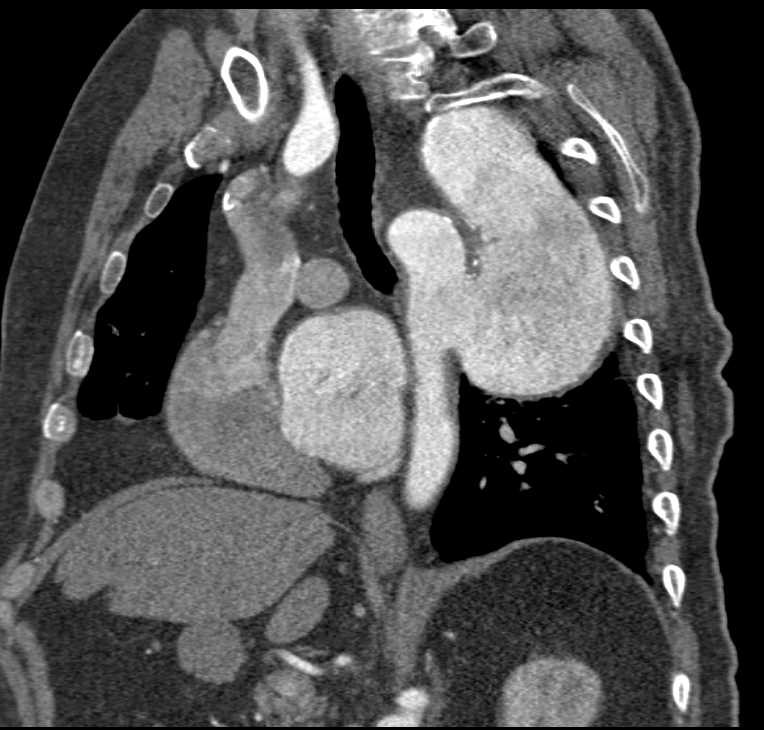

Aortic Aneurysm with Vascular Grafts